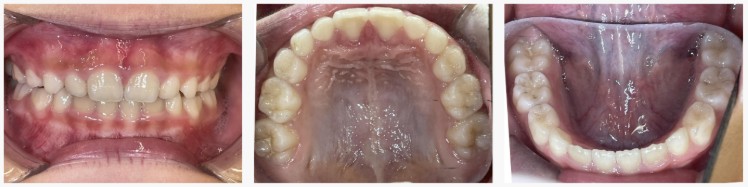

▼ After(治療後)

治療終了時には、

・永久歯が並ぶスペースが十分に確保

・歯列のアーチが整い、バランスの良い歯並びへ改善

・口呼吸や舌の位置などの習癖も改善

見た目だけでなく、機能面でも良好な変化が得られました。

早期に介入できたことで、将来抜歯をせずに矯正を進められる可能性が高くなったケースです。